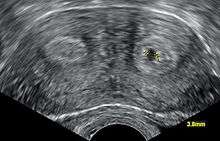

It is possible to diagnose a bicornuate uterus using gynecologic ultrasonography,[1] specifically sonohysterography, and MRI.[2] However, as there is no indication to do such procedures on asymptomatic women, the presence of a bicornuate uterus may not be detected until pregnancy or delivery. In a C-section (usually done due to malpresentation), the irregular shape of the uterus will be apparent.